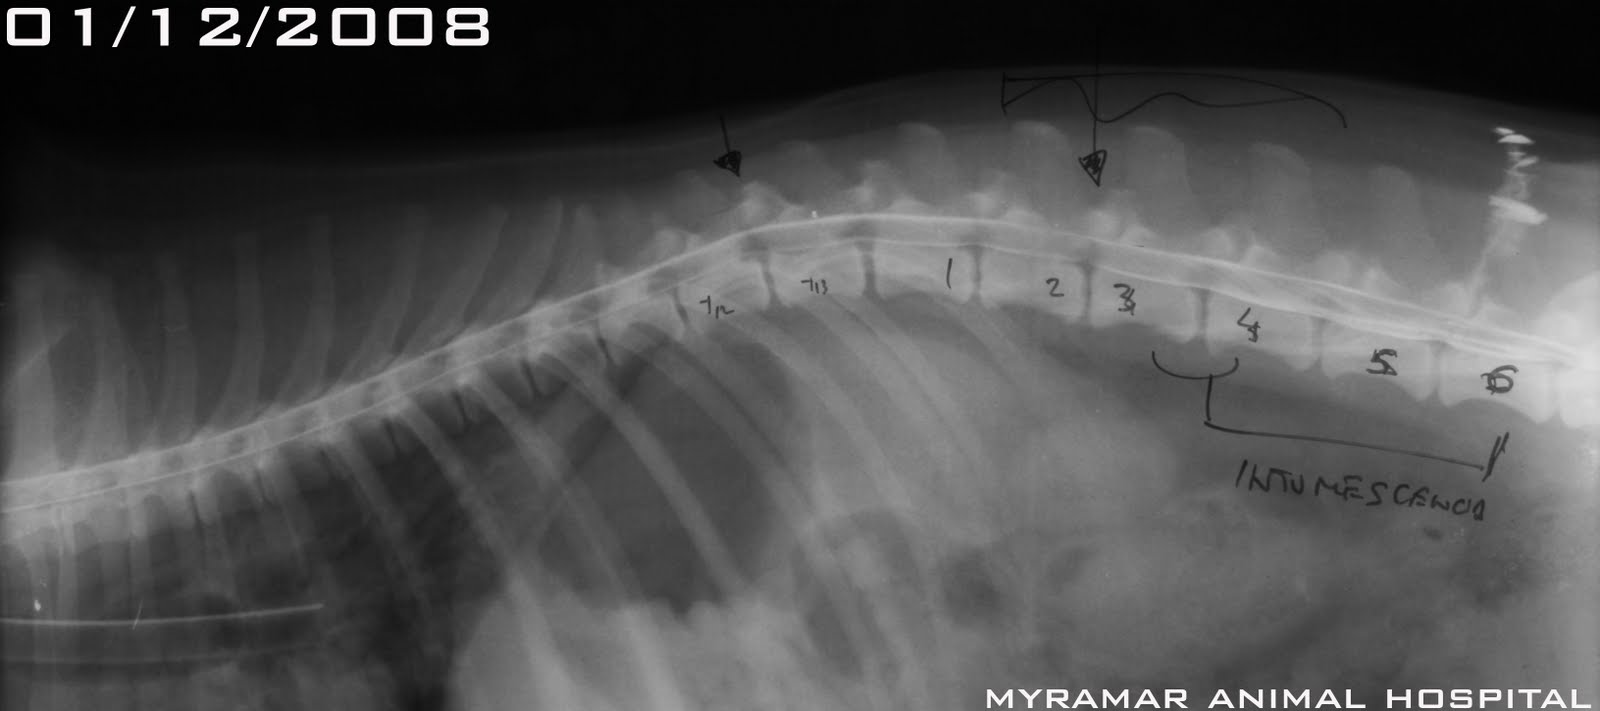

Polina, este cruce de Cocker de 8 años de edad, llega referido al hospital después de 36 horas de paraplejia.

A la exploración presenta paraparesia no ambulatoria con disminución de ambos reflejos patelares e hiperreflexia de los flexores y NO presencia de dolor profundo. La mielografía revela elevación y disminución de la columna ventral de contraste en C3-C4. Además presenta una puntual elevación en el espacio T13-L1 sin relevancia clínica.

Se presenta estudio radiológico-mielográfico del caso.